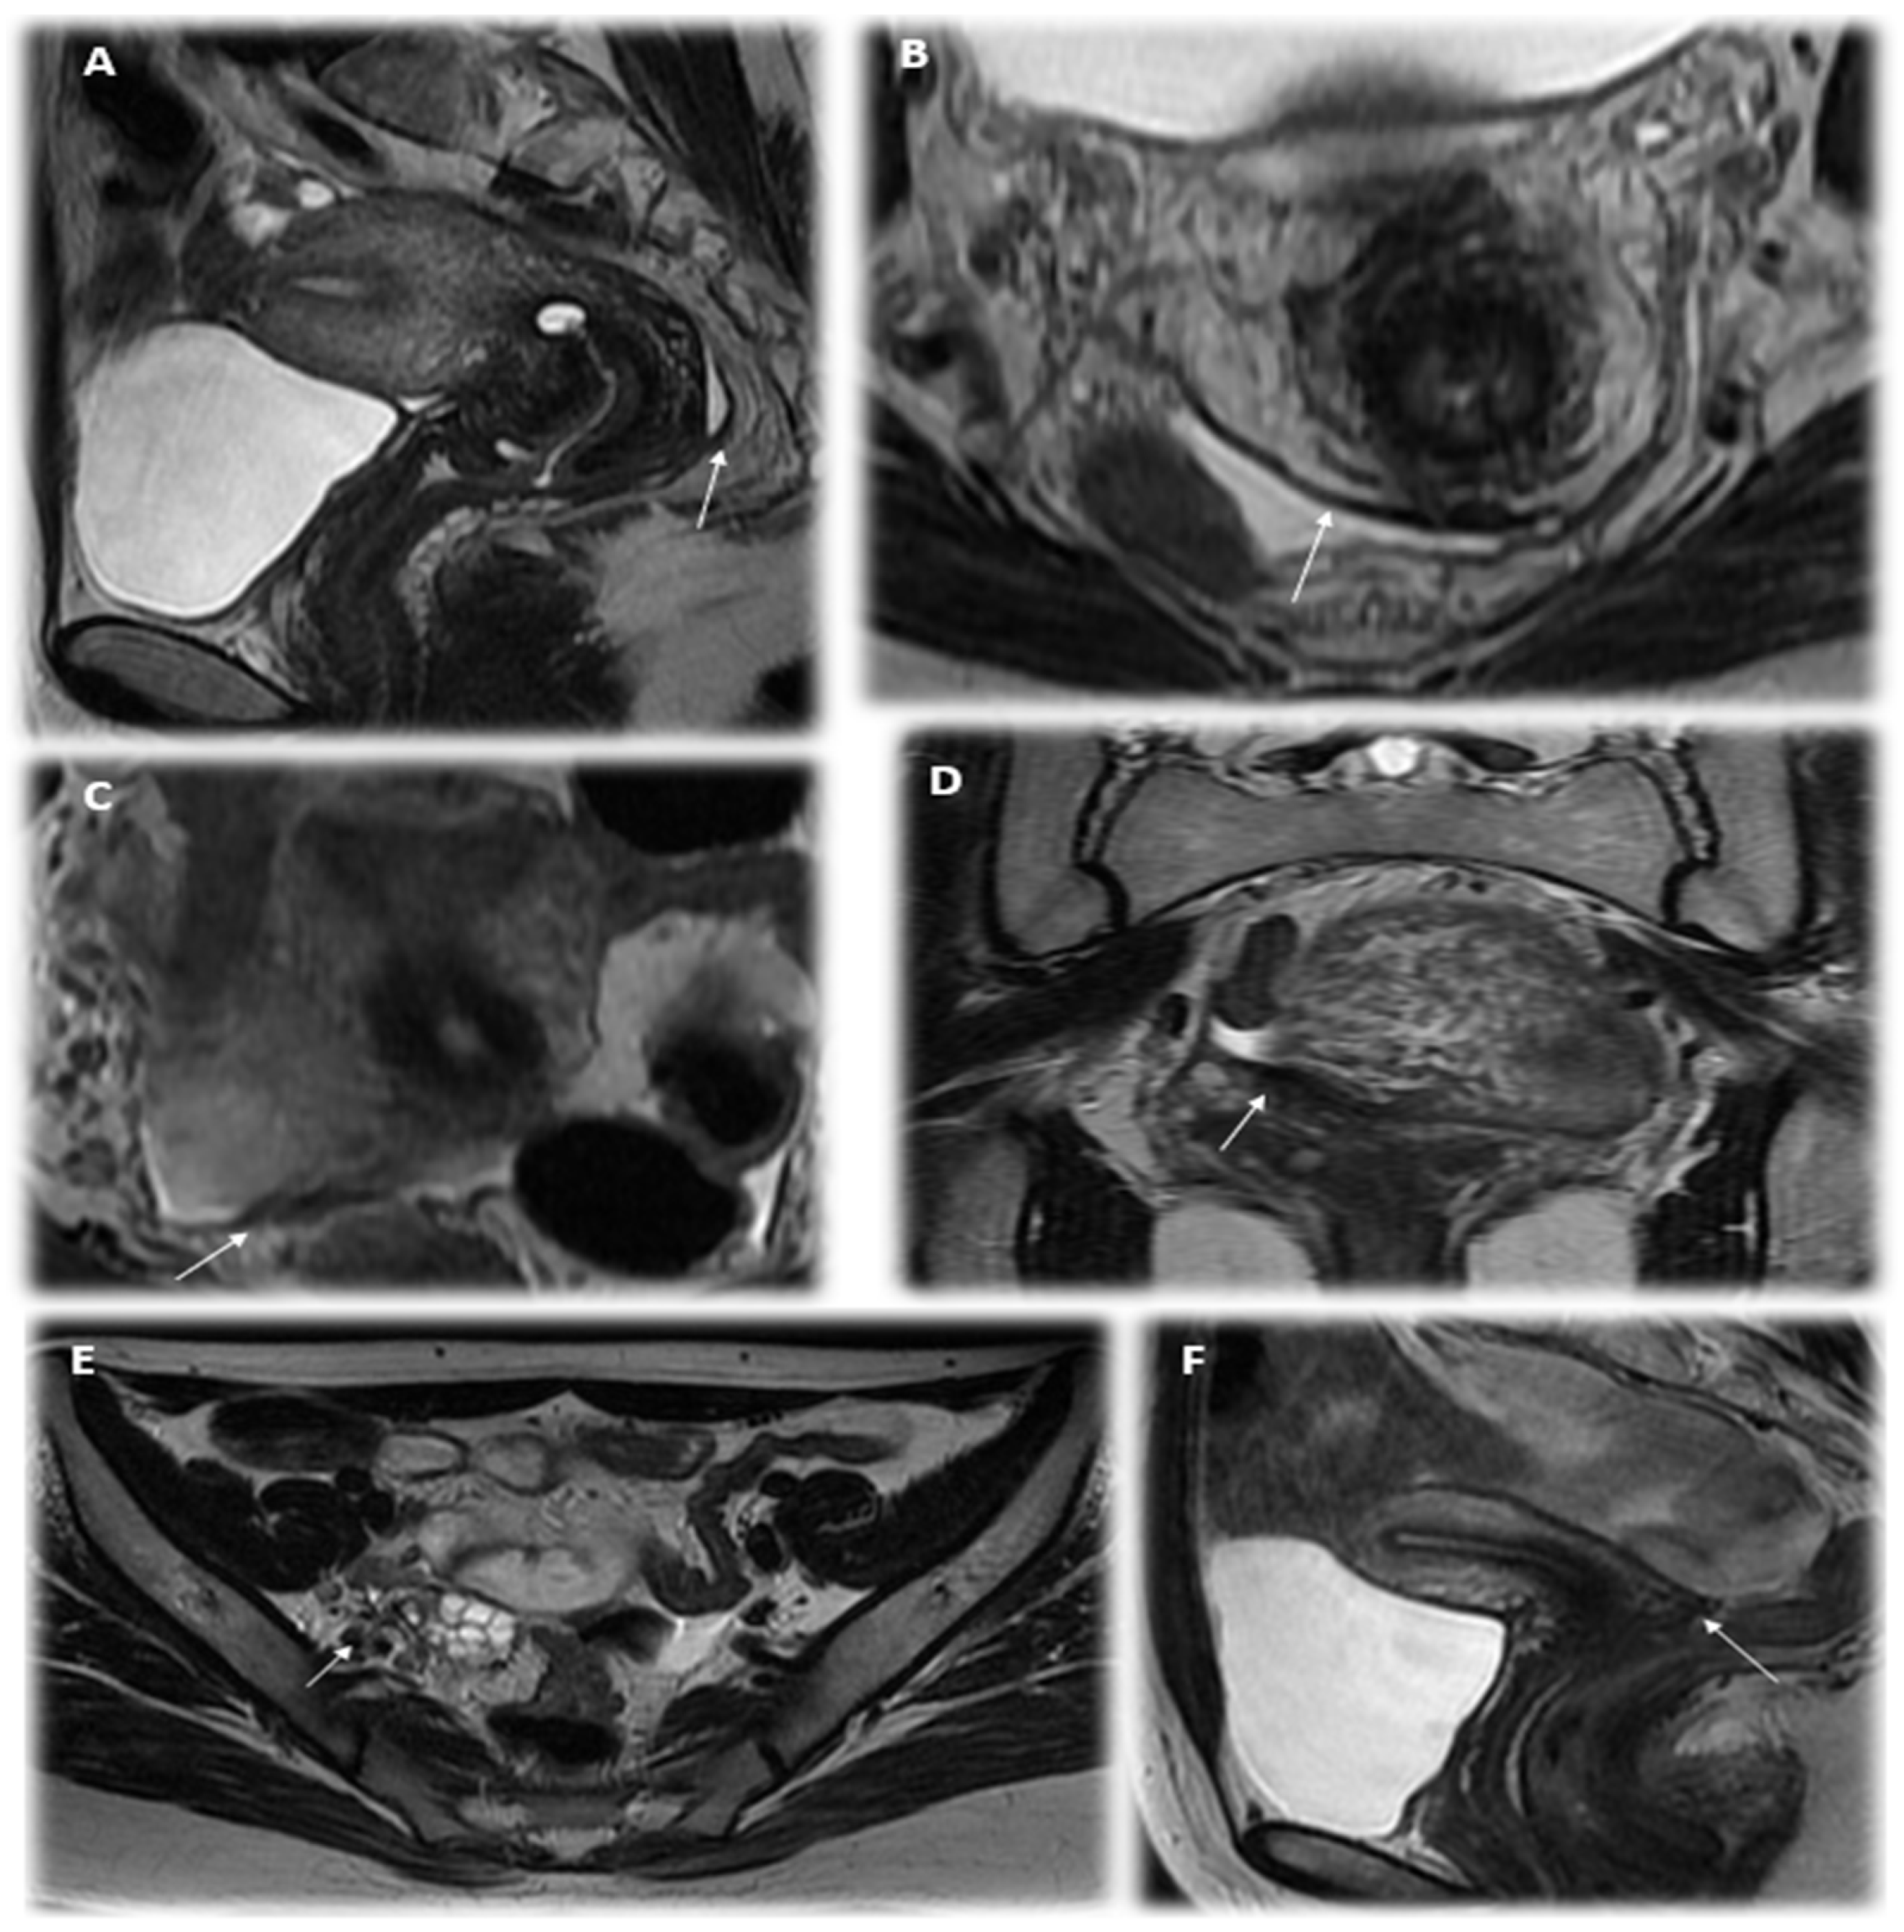

We paid special attention to the analysis of the MRI’s description in the cases of PE (Figure 2). Of the 78.9% (71) patients with verified PE according to MRI, in most cases, lesions were described on the peritoneum of the pouch of Douglas (25.4%); along the serous cover of the uterus (posterior leaf of the broad ligaments) (18.3%); on the uterosacral ligaments (39.4%); in the parametrial (38.0%), paraovarian (29.6%) and paracervical (5.6%) tissue; and suspected along the ovarian capsule (35.2%). As additional parameters, the meager amount of free fluid in the retrouterine space (63.3%; 45/71); adhesions in the pelvis, fixation of the fallopian tube, intestine and/or ovaries (32.4%; 23/71); and varicose veins of the pelvis (33.8%; 24/71) were described. These indicators could also be useful in diagnostics (see Figure 3, Table 3 and Table 4). We illustrated the most essential MRI signs in Figure 4.

Figure 4.

The MRI signs of peritoneal endometriosis in adolescents: (A)—thickening of the peritoneum and partial obliteration of the pouch of Douglas (T2VI Sag); (B)—thickening of the peritoneum of the Douglas space, free fluid and an area of low intensity of the MR signal in the projection of the uterosacral ligament on the left (T2VI Ax); (C)—the thickening of the pelvic peritoneum and the uterosacral ligament on the right (T2VI Ax); (D)—thickening of the peritoneum of the pelvic cavity and the right uterosacral ligament (T2WI Cor); (E)—the asymmetry of the structure and hypointense MR signal in the projection of the sacro-uterine ligament on the right and fixation of the right ovary (T2VI Ax); (F)—a single focus of a hypointense MR signal in the retrocervical space of small sizes (up to 0.3 cm) (T2VI Cor).

We analyzed the significance of detected MRI signs in predicting the confirmation of PE according to laparoscopy in adolescents using factor analyses. The most essential MRI signs of PE appeared to be the following: heterogeneity of paraovarian, parametrial or paracervical tissue or/and hypointense foci in the pelvic tissue, thickening or flattening of the uterosacral ligaments or asymmetric nodular irregularity of ligaments, thickening of the peritoneum and/or heterogeneity of the tissue of the pouch of Douglas, the presence of a meager amount of free fluid in the rectouterine pouch, adhesions in the pelvis and fixation of the fallopian tube, intestine and/or ovaries (see Table 3).

One of two MRI signs for ligaments or/and for the heterogeneity of the pelvic tissue provides a diagnostic accuracy of PE in 74.7% (F = 7.2, p = 0.008; area under the curve (AUC) = 0.796, p < 0.05), which could be helpful in early diagnostics (Figure 4), although it would not be enough for practical application while making a decision on whether to perform diagnostic laparoscopy. Thus, we analyzed the probability of detecting PE using laparoscopy not only according to the MRI criteria but also in combination with the clinical symptoms of persistent dysmenorrhea. The diagnostic accuracy of the parameter of persistent dysmenorrhea in predicting PE was also rather high. It appeared due to the combined use of two criteria: the complaint of persistent dysmenorrhea and positive MRI signs results in a higher accuracy of predicting the initial from of PE at 84.3% according to multivariate analysis (logistic regression model: OR 15.4, Wald’s Chi-square = 32.7, <0.001; confirmed with factorial ANOVA: F = 10.2, p = 0.002) than with the use of each index separately; the ROC analysis is presented in Figure 5. The diagnostic model, based on these parameters (persisted dysmenorrhea and one of two MRI signs), can be suggested for applications, justifying the early surgical diagnostics, shortening the time delay and suffering of the young patients and resulting in required therapy.